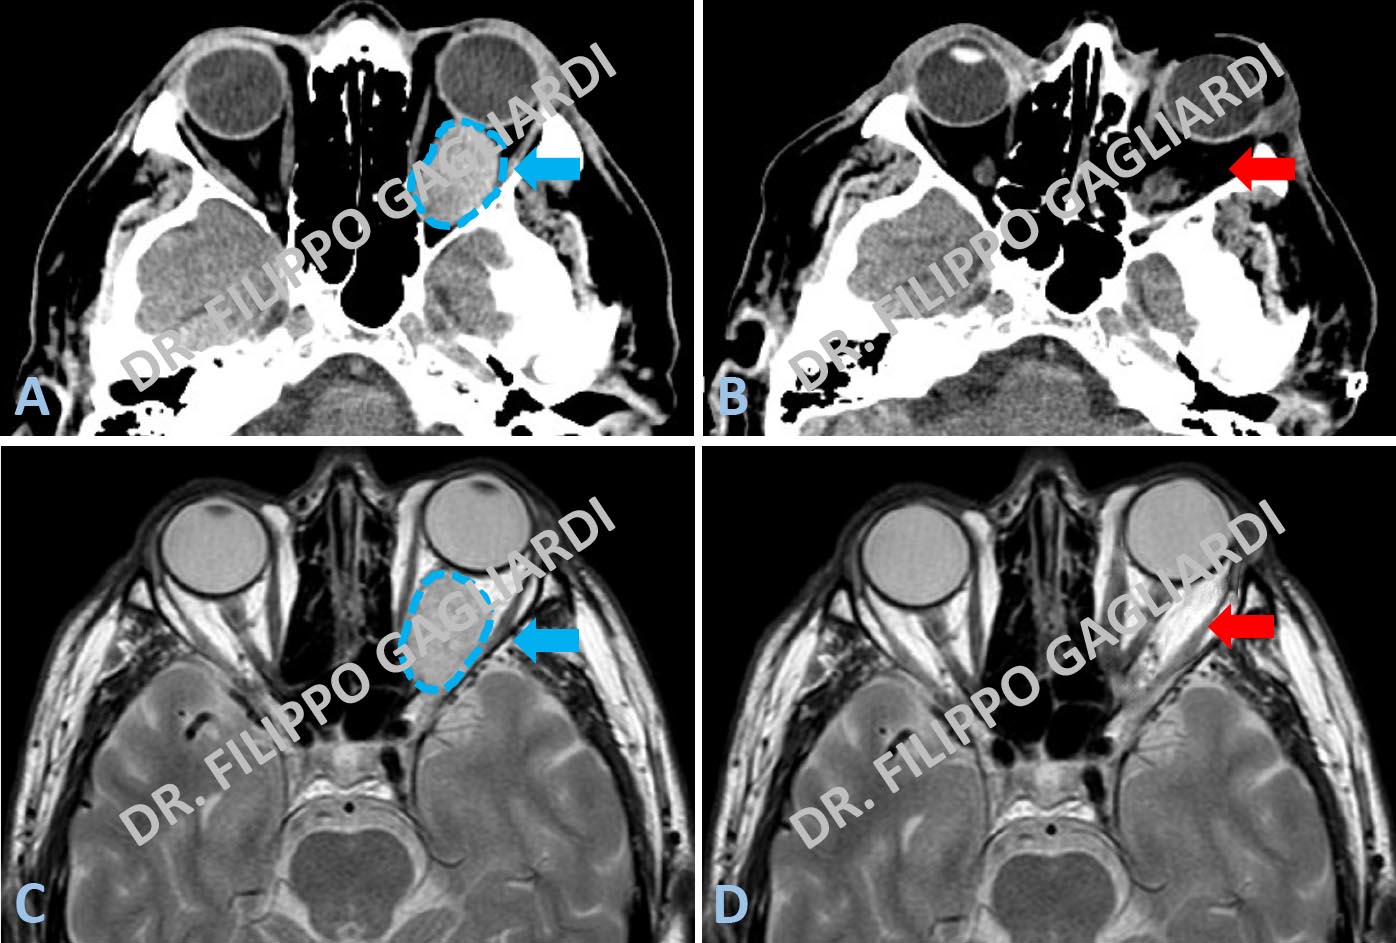

Tumori dell'orbitaCaso di angioma cavernoso orbitario sinistro (tumore vascolare dell’orbita oculare) (sagoma azzurra Figure A e C). Il tumore comprime il nervo ottico e il globo oculare che è dislocato in avanti (frecce azzurre Figure A e C). La RM e la TC post-operatorie documentano l’asportazione della lesione con la decompressione delle strutture nervose (frecce rosse Figura B e D).